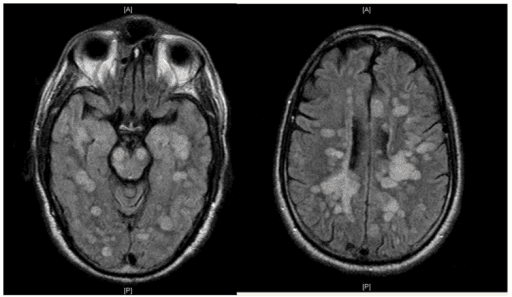

Acute disseminated encephalomyelitis (ADEM), or acute demyelinating encephalomyelitis, is a rare autoimmune disease marked by a sudden, widespread attack of inflammation in the brain and spinal cord. As well as causing the brain and spinal cord to become inflamed, ADEM also attacks the nerves of the central nervous system and damages their myelin insulation, which, as a result, destroys the white matter. The cause is often a trigger such as from viral infection or vaccinations. ADEM's symptoms resemble the symptoms of multiple sclerosis (MS), so the disease itself is sorted into the classification of the multiple sclerosis borderline diseases. However, ADEM has several features that distinguish it from MS. Unlike MS, ADEM occurs usually in children and is marked with rapid fever, although adolescents and adults can get the disease too. ADEM consists of a single flare-up whereas MS is marked with several flare-ups (or relapses), over a long period of time. Relapses following ADEM are reported in up to a quarter of patients, but the majority of these 'multiphasic' presentations following ADEM likely represent MS. ADEM is also distinguished by a loss of consciousness, coma and death, which is very rare in MS, except in severe cases. It affects about 8 per 1,000,000 people per year. Although it occurs in all ages, most reported cases are in children and adolescents, with the average age around 5 to 8 years old. The disease affects males and females almost equally. ADEM shows seasonal variation with higher incidence in winter and spring months which may coincide with higher viral infections during these months. The mortality rate may be as high as 5%; however, full recovery is seen in 50 to 75% of cases with increase in survival rates up to 70 to 90% with figures including minor residual disability as well. The average time to recover from ADEM flare-ups is one to six months. ADEM produces multiple inflammatory lesions in the brain and spinal cord, particularly in the white matter.